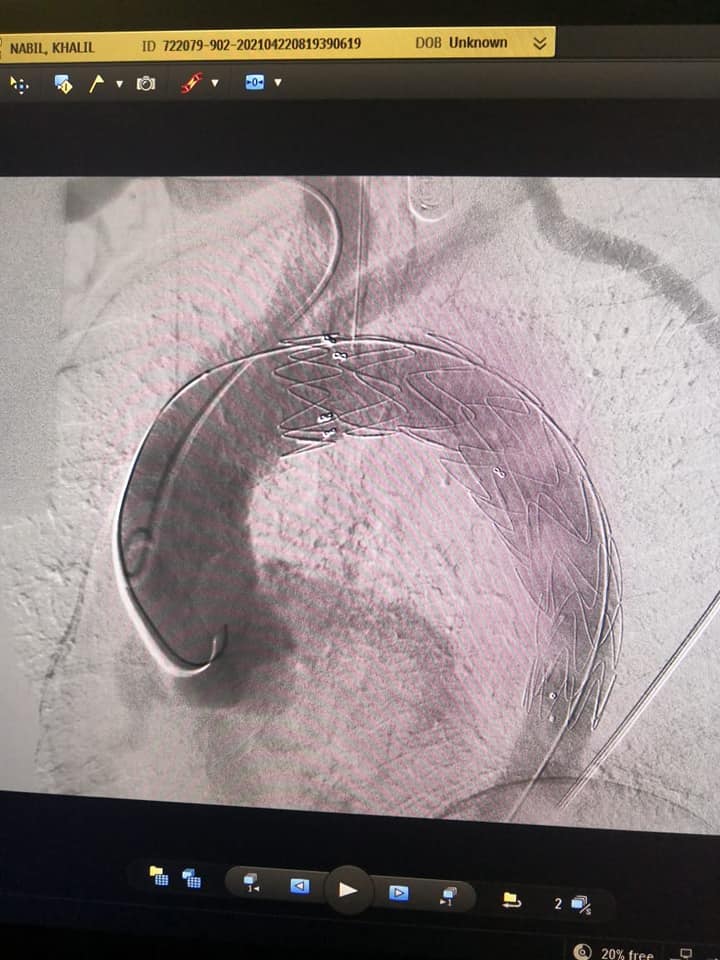

إجراء أول حالة «تيفار» بمركز جراحة الأوعية الدموية بجامعة المنصورة

قام فريق من جراحي الأوعية الدموية برئاسة الدكتور مسعد سليمان مدير مركز جراحة الأوعية الدموية، وبحضور ممثلين لجراحي القلب وفريق العناية، بإجراء قسطرة تداخلية لتصحيح انشطار بشريان الأورطي الصدري نتيجة الارتفاع المزمن بضغط المريض، وأدى الانشطار إلى تمدد بشريان الأورطي منذرا بحدوث انفجار علاوة على توقف الدورة الدموية عن بعض الأعضاء الحيوية.

و تم توفير كافة مستلزمات الجراحة بواسطة إدراة العلاج ضمن قوائم الانتظار وتم إجراء التدخل بواسطة تقنية الدعامات المغطاة والتي تضمن إعادة سريان الدم في الشريان الأورطي الرئيسي واستغرقت ٤٥ دقيقة مع توفير كافة الاستعدادات من فريق جراحة القلب وكذلك من فريق التخدير برئاسة الدكتورة دعاء جلال وفريق العناية المركزة برئاسة الدكتورة محمد عادل وأظهرت فحوصات المريض فور انتهاء الايفار بنجاح التدخل بنسبة ١٠٠٪.